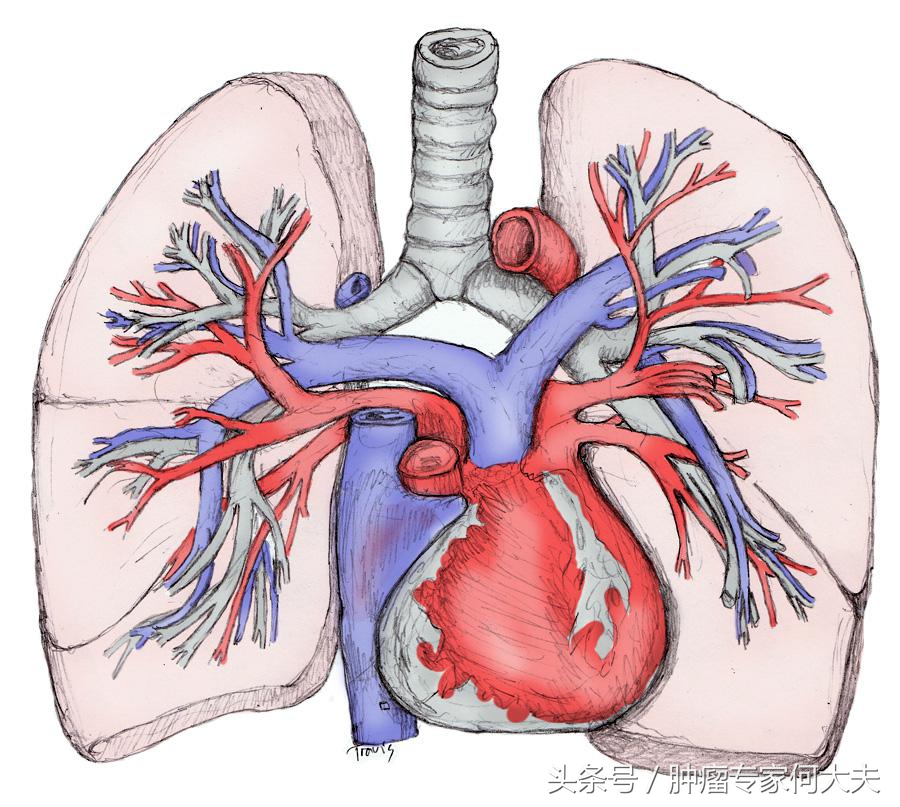

肺和血管